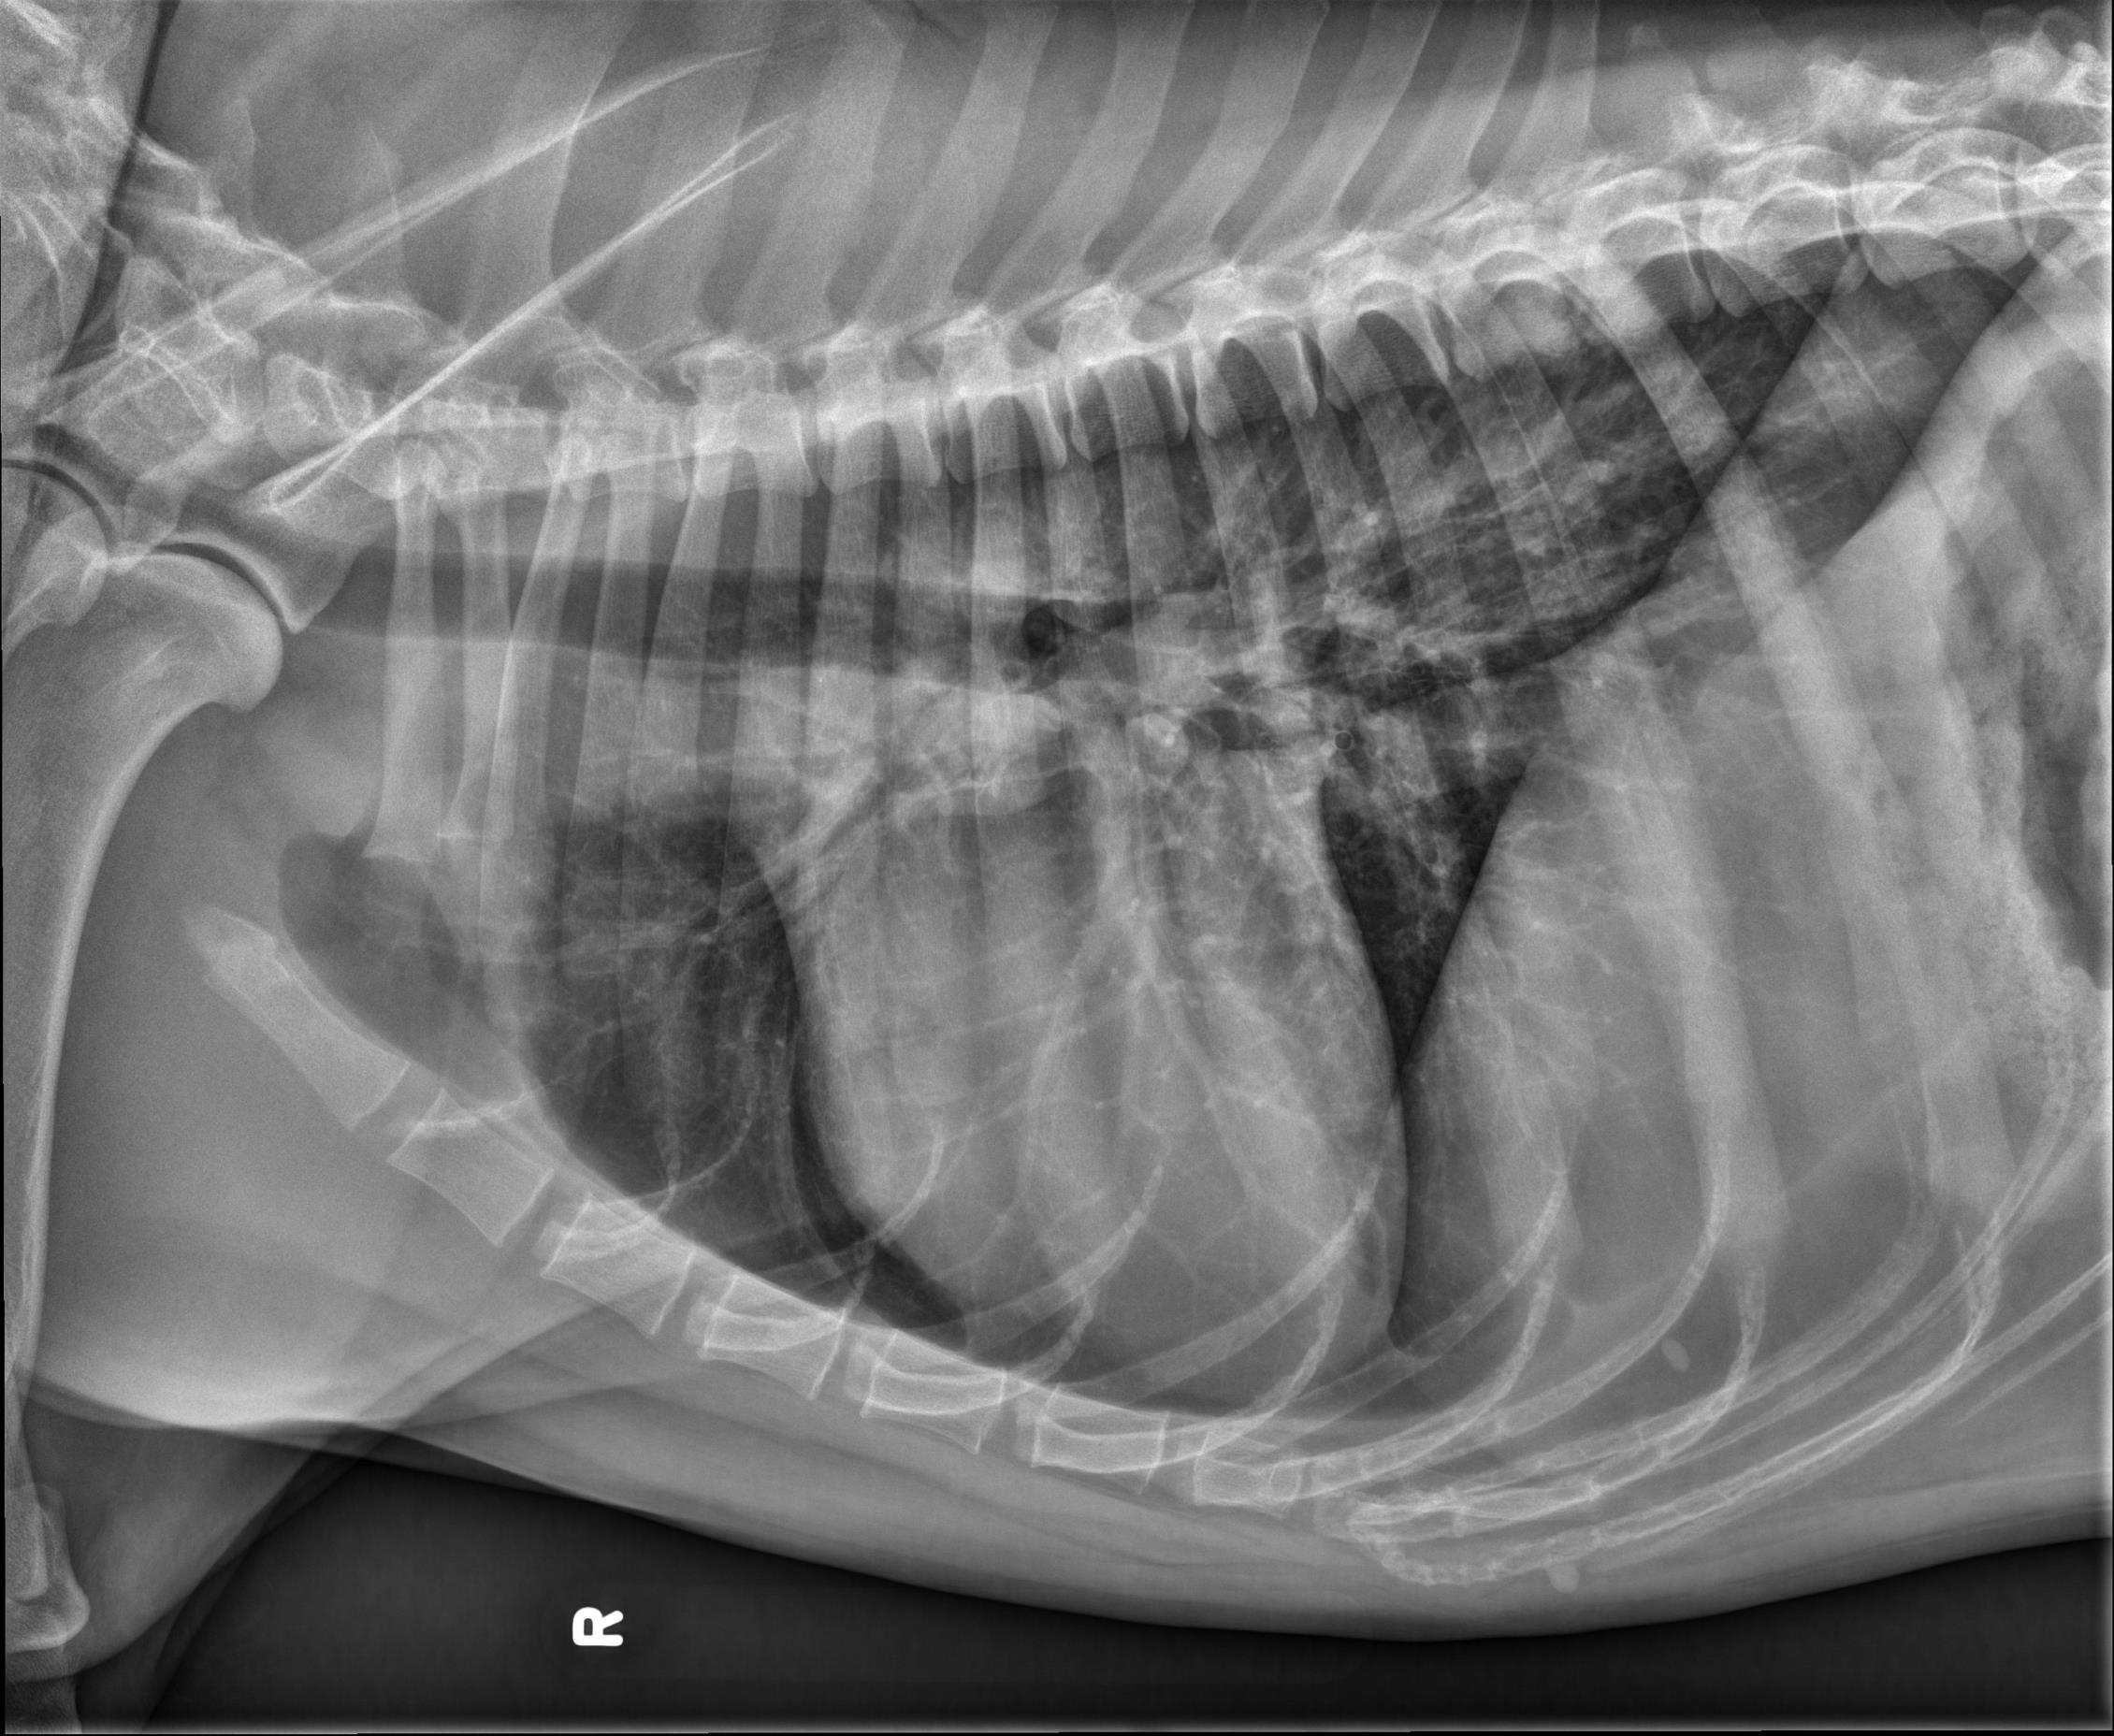

Thorax ventrodorsal and lateral radiographs are available for interpretation.

Thorax: The pulmonary parenchyma is normal. The cardiac silhouette and pulmonary vessels are normal. The pleural and mediastinal spaces are normal.

There is mild to moderate osteolysis of the caudal endplate of T9 and the cranial endplate of T10 which is surrounded by sclerotic bone. The T9-10 intervertebral disc space is narrowed.

The appearance of the T9-10 intervertebral disc space is most concerning for discospondylitis.